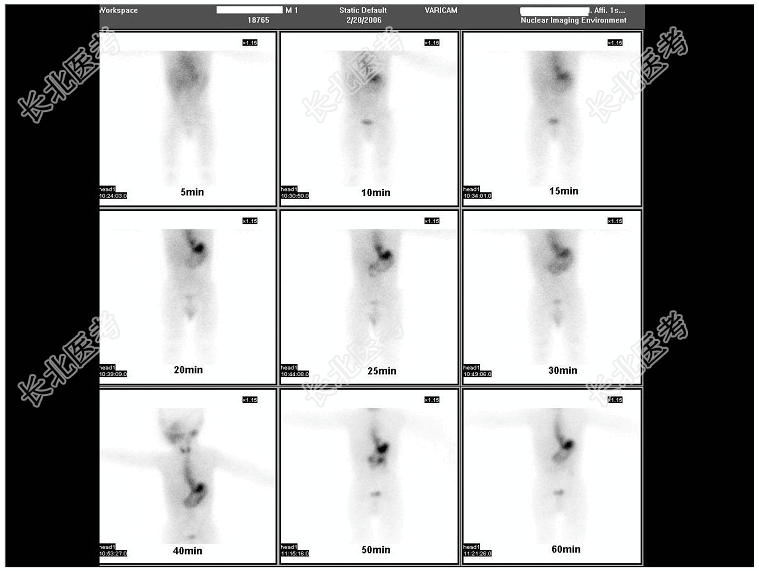

- [材料题] 1岁男孩,反复呕吐多次,均呈咖啡色,血红蛋白偏低,行⁹⁹TcᵐO₄⁻腹部显像如图: